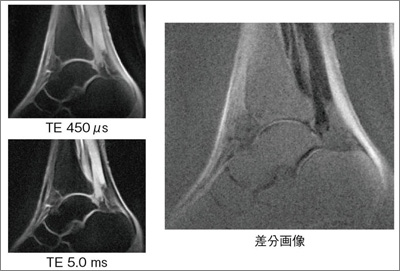

μTE(TE短縮の新しいコントラスト画像)

■μTE(TE短縮の新しいコントラスト画像)

μTE計測機能は,T2値が非常に短い組織(1ms以下)を撮像する機能です。パルスシーケンスには2D GREをベースとしたハーフエコーのRADAR(ラジアル)計測を用います。

図5に,撮像原理を示します。TEを限界まで短縮するために,k空間の充填を中心から行うようにシーケンスを制御します。このため,RADARと同様の画像再構成技術が適用されます。

μTEでは,きわめて短いTE(第1エコー)で計測した画像と長いTE(第2エコー)で計測した画像を差分し,長いT2成分のみを除去した画像を出力できます(図6)。これにより,非常に短いT2組織の検出や画像化を実現し,軟骨粗鬆症の初期評価などに期待されています。また,高速な撮像切替えに対応した専用の高速受信コイルも新開発しました。

![]() 図6 アキレス腱画像 |